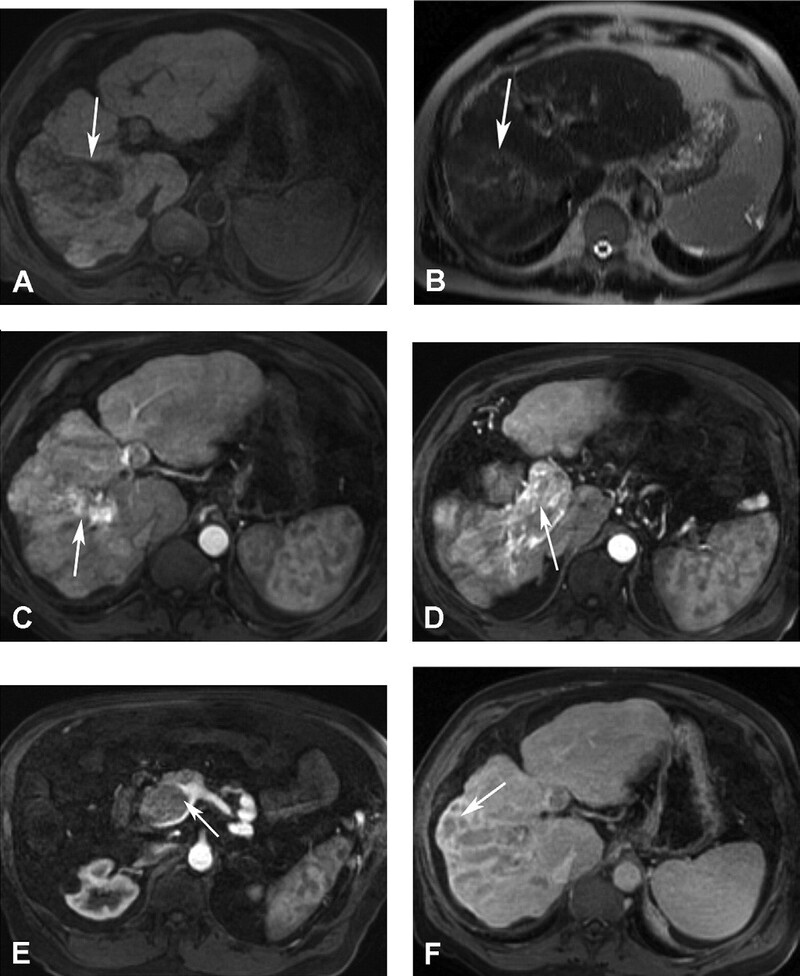

Di căn đến gan từ các u nguyên phát như u tế bào tiểu đảo/thần kinh nội tiết, carcinoid, carcinoma tế bào thận, melanoma và carcinoma tuyến giáp thuộc về nhóm di căn gan giàu mạch máu. Trên siêu âm di căn là các tổn thương giảm âm. Vùng trung tâm hoại tử có thể giảm âm hoặc echo trống. Hầu hết di căn giảm đậm độ trên CT không cản quang. Di căn của u thần kinh-nội tiết có thể tăng đậm độ trên CT không cản quang. Hầu hết các di căn giàu mạch máu bắt quang sớm mô u sống ở thì động mạch và giảm đậm độ với nhu mô gan ở thì tĩnh mạch cửa (Hình 14-18). T2W có tín hiệu thay đổi, thường tăng tín hiệu trung bình và giảm tín hiệu trên T1W, Melanoma là một ngoại lệ, ở đó tích tụ melanin, có tính chất rút ngắn thời gian T1, có thể dẫn đến tín hiệu cao trên T1W (Hình 19). Bắt Gd đặc trưng cho thấy tổn thương rõ rệt nhất ở thì động mạch với viền bắt thuốc ngoại vi điển hình (Hình 20C).

Hình 17. U tế bào tiểu đảo di căn gan. Nhiều ổ di căn ấyở gan là các ổ giảm tín hiệu trên T1W (A) và tăng tín hiệu trên T2W (B). Ghi nhận khối lớn nhất cấp máu quá mức và gây hoại tử trung tâm có tín hiệu thấp trên T1W (A, mũi tên) và tín hiệu cao trên T2W (B, mũi tên). Tất cả các tổn thương bắt thuốc viền ngoại vi mạnh ở thì động mạch (C, tổn thương lớn nhất được đánh mũi tên), thải thuốc nhanh ở thì tĩnh mạch cửa (D, tổn thương lớn nhất được đánh mũi tên). Vùng trung tâm trong tổn thương lớn nhất (mũi tên ở E) nghèo mạch máu và không bắt thuốc ở thì động mạch, nhưng thường có thể tụ tập thuốc tương phản ở thì mô kẽ trễ.